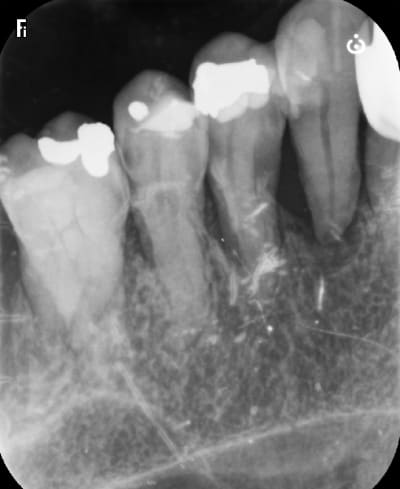

c est une béance avec 24 et 25 très mobile , enfin elles l étaient avant le prov .

c est un pb ce zircon full , en fait c est une grosse merde . surtout ces zircons jolis c est fragile pour les bridges .

d un autre coté , sur un cas comme ça , si tu fais de la ccm alors là c est sur que tu as un pb paro tout de suite avec perte des dents rapidement .

du coup , quoi faire d autre ? devant c est un bridge que j ai fait en 2018 et c était bien pire , en attendant les implants qu elle n a jamais fait .

là on voit bien la double limite : la limite tres fine ne peut pas casser pcq ce n est pas elle qui evite l'enfoncement . et l'épaisseur du joint est infime .